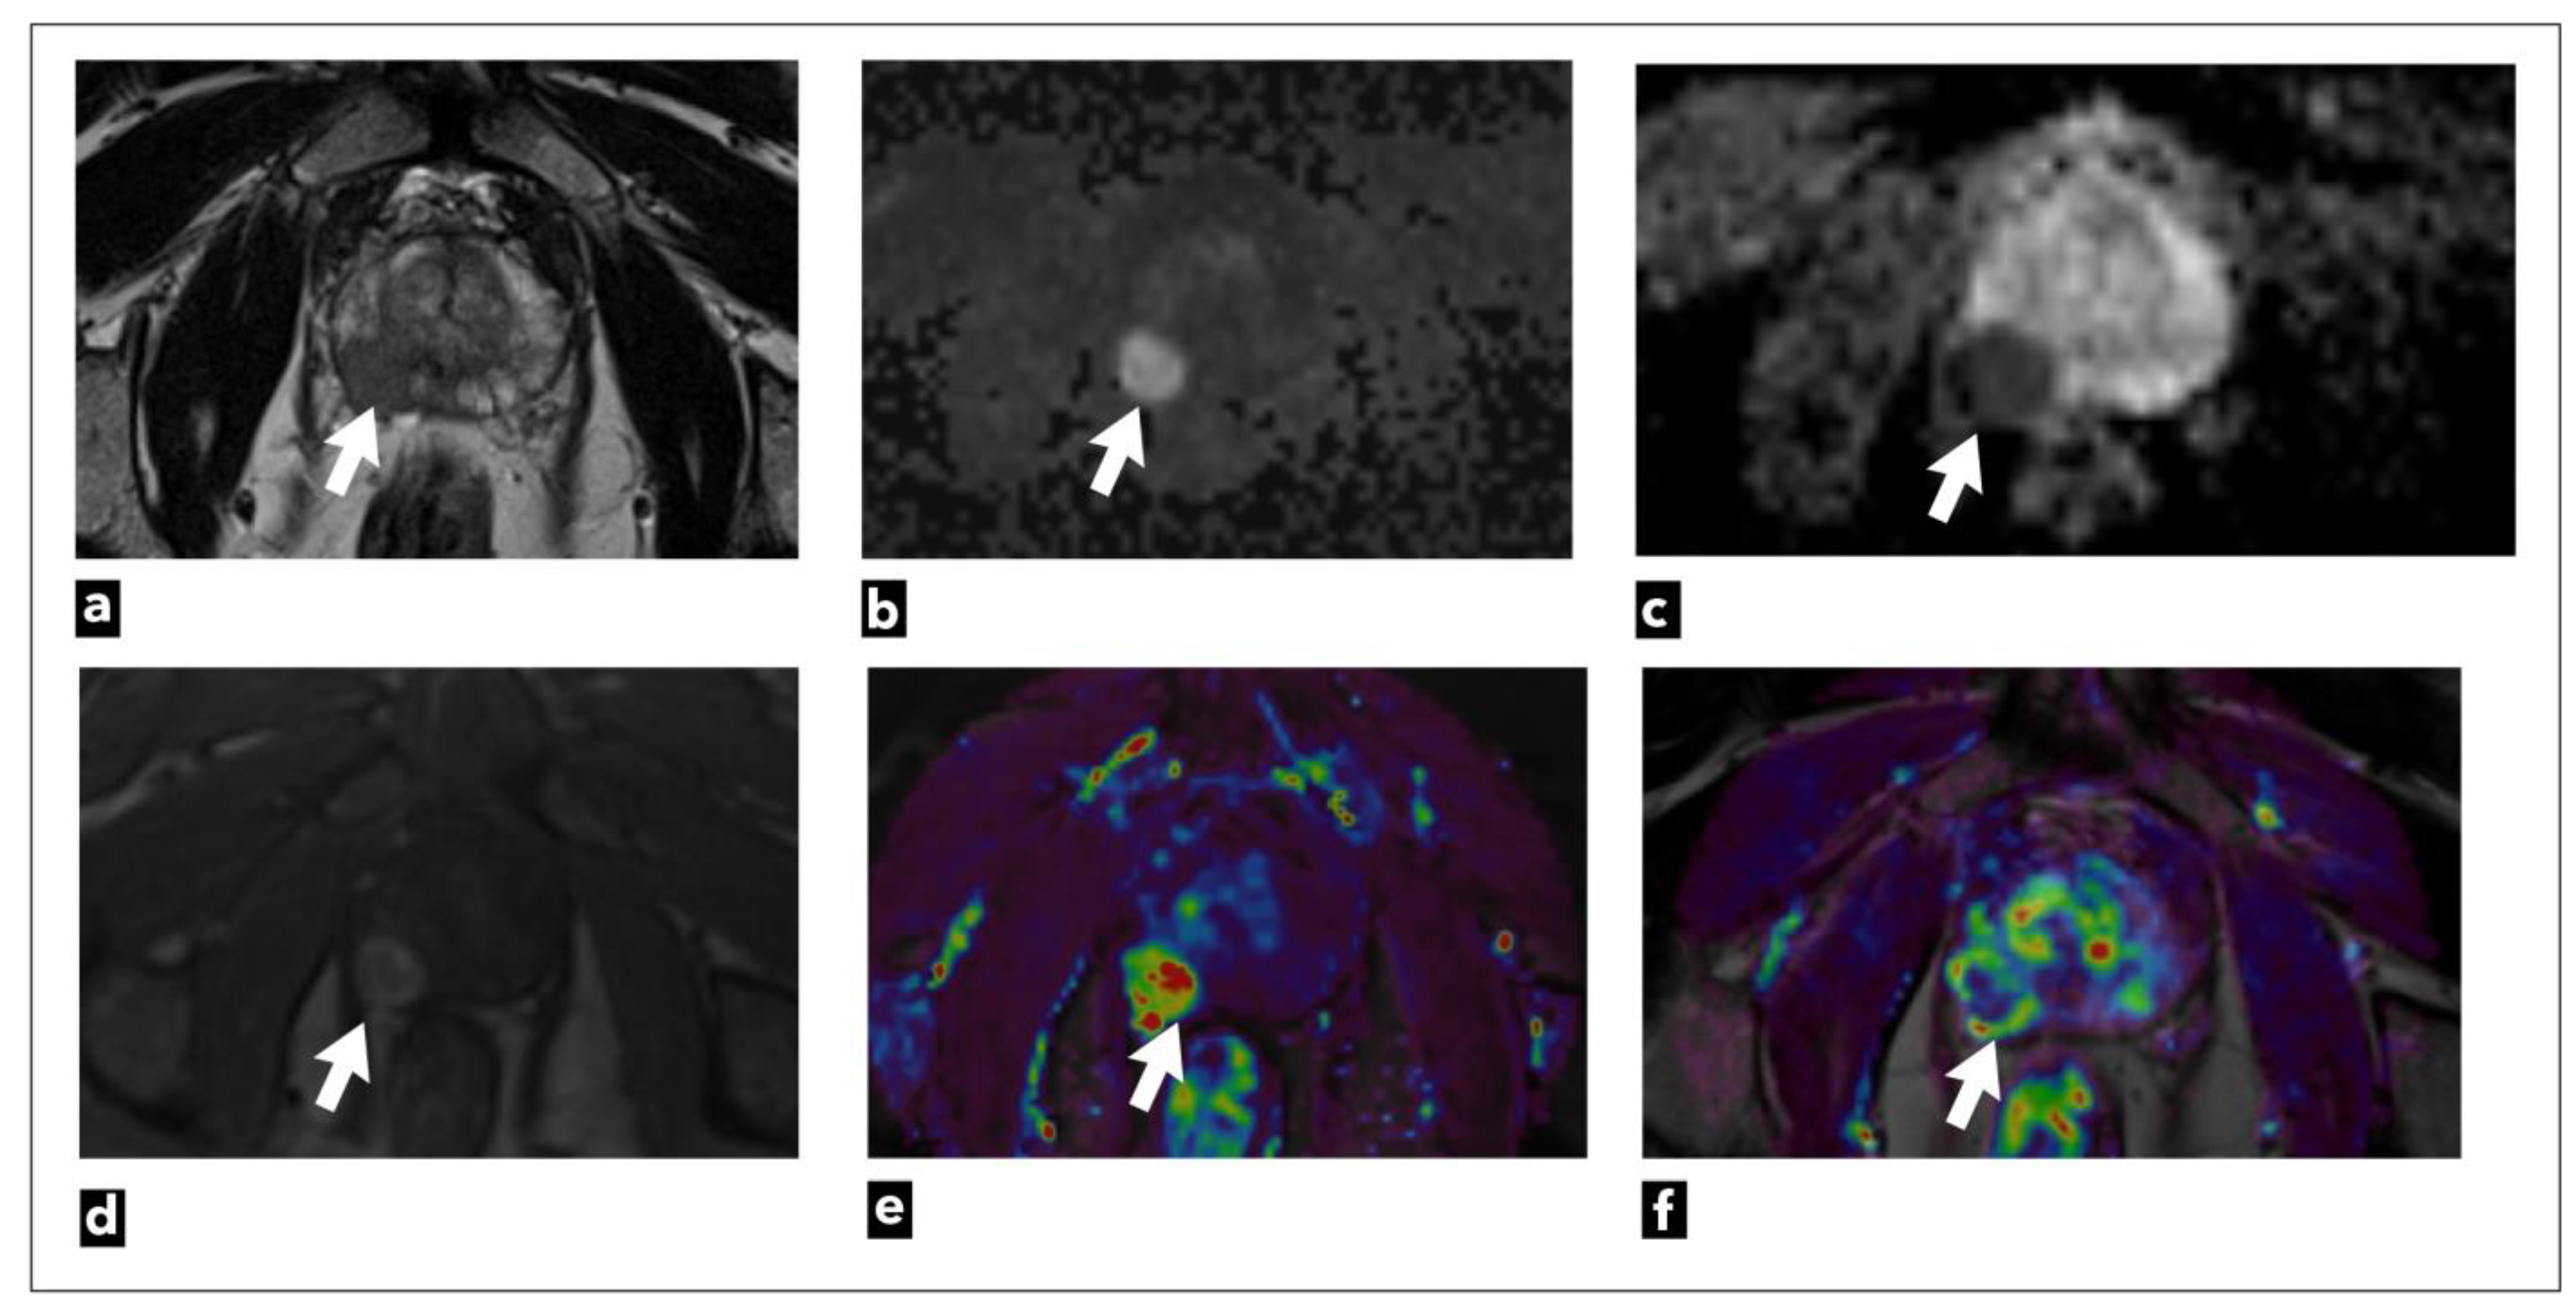

There are three analytic approaches to DCE-MRI analysis: qualitative, semi-quantitative, or quantitative [47]. Also, it can be analysed from raw data or using coloured parametric maps (Figure 2).

The currently valid PI-RADS v2.1 categorisation includes qualitative visual analysis, the simplest method of analysis, since it does not require special software, but can be analysed using a simple Picture Archiving and Communication System (PACS) workstation. This method relies only on the visual assessment of early arterial contrast accumulation in lesions previously observed as suspicious on T2W and DWI sequences. If early contrast accumulation is observed, the DCE-MRI finding is considered positive. However, DCE-MRI is considered negative [13] if early contrast accumulation is not observed or if diffuse contrast accumulation that does not correspond to the location of the T2W/DWI suspicious lesion is observed. The disadvantage of this method is the lack of standardisation and objectivity since interpretation is based on subjective assessment [47].

The second analytic method is a semi-quantitative method that analyses the kinetics of contrast accumulation on the observed lesion, wash-in, i.e., the arrival of the contrast agent in the lesion, wash-out, time to peak (TTP), and peak enhancement (PE) [48]. Using special software, the signal-intensity time curves are created [47]. There are three types of curves: type 1 curve (progressive) is a persistent curve in which there is a gradual increase in contrast accumulation and it is characteristic of benign changes; type 2 curve (plateau) is a curve in which there is an early and sudden contrast accumulation followed by a plateau; it can be seen in both benign and malignant focal lesions; and type 3 curve (wash-in and wash-out), a curve where there is an early and sudden accumulation of contrast followed by wash-out of the contrast agent, and this type of curve indicates the presence of prostate cancer (Figure 3) [49].

Using kinetic curves is a visually simple and easy-to-use method of analysis, but the shape of the curve highly depends on the injection quality, which makes it less reproducible [37]. Also, motion artifacts that result from peristalsis or patient motion artifacts can result in misregistration between successive slices, which is seen as noise in the curves. Special software used for image post-processing enables automatic correction of motion artifacts [13]. Parameters obtained with this method can be displayed and analyzed as parametric coloured maps which are fused with the T2W sequence for easier anatomical orientation [50].

The disadvantage of this method is that the values are estimated only based on the change in signal intensity in the observed lesion, without a physiological or empirical model, and the change in signal intensity in the tissue depends on the parameters that are not taken into account with this method like sequence parameters, the dose and type of injected contrast agent and on the characteristics of the tissue itself [48].

Also, this method has a weak possibility of distinguishing between benign and malignant lesions since all three curves can be seen in both benign and malignant lesions, and according to some research, there is a lack of reproducibility and accuracy of this method [51]. Mainly due to these reasons, the semiquantitative method, which was initially included in PI-RADS v.1 was removed from PI-RADS v.2.(8-10).

The third analytic method is the quantitative method, which is the most sophisticated DCE method. It is based on the measurement of pharmacokinetic parameters using one of the pharmacokinetic models [49]. The most commonly used Tofts model [52].

The parameters obtained using this method are Ktrans (constant of transendothelial transfer of contrast medium from intravascular space to extravascular extracellular space), Kep (constant of transendothelial transfer of contrast from extravascular extracellular space back to intravascular space), Vp (plasma volume in relation to total volume tissue), and Ve (tumour extravascular extracellular space volume) [2,53]. These parameters provide information about microvascular permeability in observed tissue [54]. The obtained parameter values can also be displayed and analysed as parametric coloured maps fused with the T2W sequence for easier anatomical orientation. Time-concentration curves can be generated with this method using special software.

The signal intensity of some tissue seen on DCE-MRI is not proportional to contrast concentration in that tissue, and therefore pharmacokinetic models take into account the amount and concentration of contrast as well as the time of contrast arrival in the supplying blood vessel (arterial input function; AIF) [2,48,52,55]. AIF can be determined individually, or population-based AIF can be used [56]. Individual AIF is more patient-specific because every patient has a different haemodynamic characteristic (heart rate, blood volume), but it is considered valid to use population-based AIF in clinical use since it is time-saving, and less operator-dependent [57].

Research analysing parameters in this method has shown that there are increased values of Ktrans and Kep in prostate cancer compared to normal prostate tissue [14].

This method also requires special software, which makes it currently less available in everyday clinical practice. Furthermore, it prolongs the time required for the analysis of the obtained magnetic resonance images and may also give abnormal findings in cases of some benign changes, such as nodules in BPH, or prostatitis [58]. This method is also influenced by motion artifacts since they can make noise in curves and lead to several limitations in curve fitting with the pharmacokinetic model. However, software can automatically reposition the successive slices so that they align better [13].

For these reasons, this method was not included in PI-RADS v.1 nor in PI-RADS v.2, but research dealing with this method shows the advantages of this method and the possibility of its implementation in everyday clinical practice. In magnetic resonance imaging of other organic systems, this method has been proven effective and applicable [59,60,61,62].